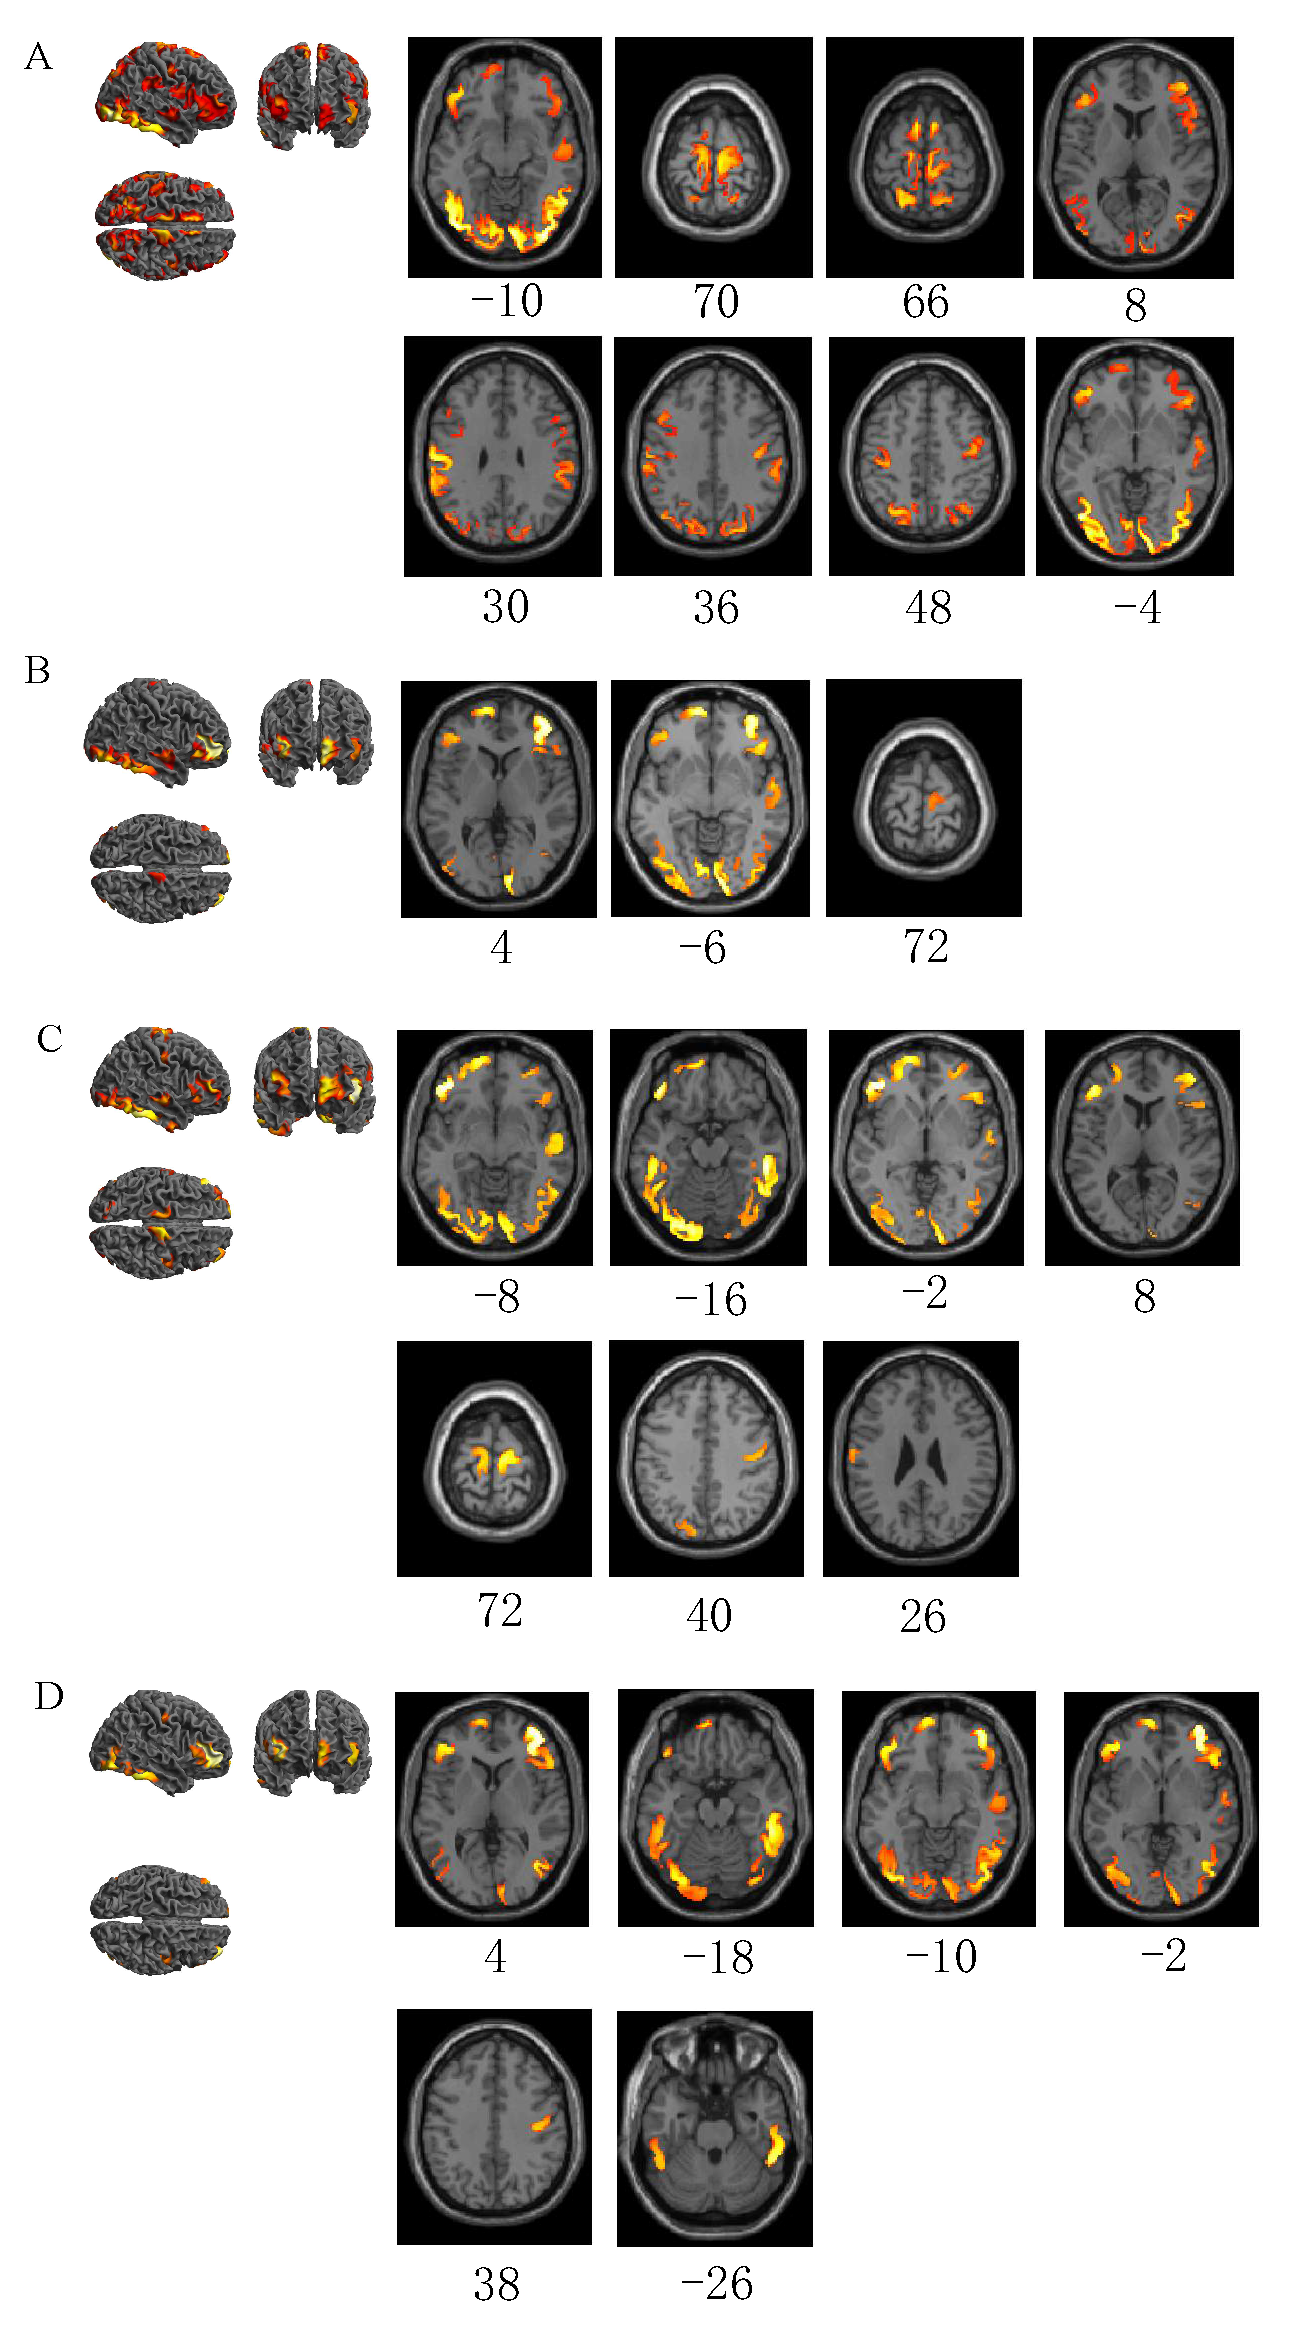

3.2. Differences in Brain Area Activation between Distracted Driving Emergency Braking and Normal Driving

| Emergency braking in normal driving vs. normal driving | −46 | −78 | −10 | 9386 | 12.60 | L | Inferior occipital gyrus |

| 6 | −24 | 70 | 1689 | 8.90 | R | Paracentral lobule | |

| −6 | 10 | 66 | 367 | 8.64 | L | Supplementary motor areas | |

| 8 | 12 | 64 | 260 | 8.60 | R | Supplementary motor areas | |

| −42 | 38 | −14 | 778 | 8.37 | L | Inferior frontal gyrus, orbital part | |

| −22 | −62 | 62 | 1978 | 8.09 | L | Superior parietal gyrus | |

| 44 | 46 | 8 | 1763 | 7.58 | R | Middle frontal gyrus | |

| 52 | −32 | 30 | 464 | 6.60 | R | Supramarginal gyrus | |

| 40 | −16 | 36 | 677 | 6.59 | R | Postcentral gyrus | |

| −36 | −24 | 48 | 493 | 6.57 | L | Postcentral gyrus | |

| 58 | −4 | −4 | 358 | 6.02 | R | Superior temporal gyrus | |

| −46 | 14 | 38 | 198 | 5.84 | L | Middle frontal gyrus | |

| −12 | 58 | −16 | 322 | 5.31 | L | Superior frontal gyrus, orbital part | |

| Emergency braking in visual distraction driving vs. normal driving | 8 | −84 | −10 | 2205 | 8.81 | R | Lingual gyrus |

| 44 | 50 | 4 | 1144 | 8.48 | R | Middle frontal gyrus | |

| −12 | 64 | −2 | 546 | 7.89 | L | Middle frontal gyrus, orbital part | |

| −8 | −80 | −6 | 2353 | 7.46 | L | Lingual gyrus | |

| 56 | −4 | −6 | 353 | 5.33 | R | Superior temporal gyrus | |

| −40 | 40 | −6 | 421 | 5.30 | L | Inferior frontal gyrus, orbital part | |

| 8 | −20 | 72 | 107 | 4.03 | R | Supplementary motor area | |

| Emergency braking in auditory distraction driving vs. normal driving | −40 | 40 | −8 | 682 | 8.20 | L | Inferior frontal gyrus, orbital part |

| 52 | −36 | −16 | 2411 | 8.08 | R | Inferior temporal gyrus | |

| −24 | −86 | −16 | 2746 | 7.52 | L | Lingual gyrus | |

| 14 | −98 | −2 | 421 | 6.86 | R | Calcarine fissure and surrounding cortex | |

| −14 | 64 | −2 | 925 | 6.63 | L | Middle frontal gyrus, orbital part | |

| 46 | 46 | 8 | 644 | 6.47 | R | Middle frontal gyrus | |

| 12 | −16 | 72 | 341 | 6.40 | R | Supplementary motor area | |

| 44 | 30 | 0 | 342 | 5.86 | R | Inferior frontal gyrus, triangular part | |

| 58 | −4 | −6 | 309 | 5.29 | R | Superior temporal gyrus | |

| −10 | −24 | 74 | 228 | 5.24 | L | Paracentral lobule | |

| 42 | −14 | 36 | 306 | 4.85 | R | Postcentral gyrus | |

| −10 | −84 | 40 | 120 | 4.29 | L | Cuneus | |

| −62 | −10 | 26 | 175 | 4.24 | L | Postcentral gyrus | |

| Emergency braking in cognitive distraction driving vs. normal driving | 44 | 50 | 4 | 767 | 11.08 | R | Middle frontal gyrus |

| 52 | −38 | −18 | 1258 | 9.42 | R | Inferior temporal gyrus | |

| −44 | −80 | −10 | 420 | 8.87 | L | Inferior occipital gyrus | |

| −44 | 34 | −16 | 438 | 8.48 | L | Inferior frontal gyrus, orbital part | |

| −10 | 64 | −2 | 256 | 8.07 | L | Middle frontal gyrus, orbital part | |

| 48 | 32 | −2 | 262 | 7.77 | R | Inferior frontal gyrus, orbital part | |

| 14 | −98 | −2 | 142 | 6.90 | R | Calcarine fissure and surrounding cortex | |

| 40 | −16 | 38 | 198 | 6.33 | R | Postcentral gyrus | |

| −50 | −44 | −26 | 291 | 6.33 | L | Inferior temporal gyrus | |